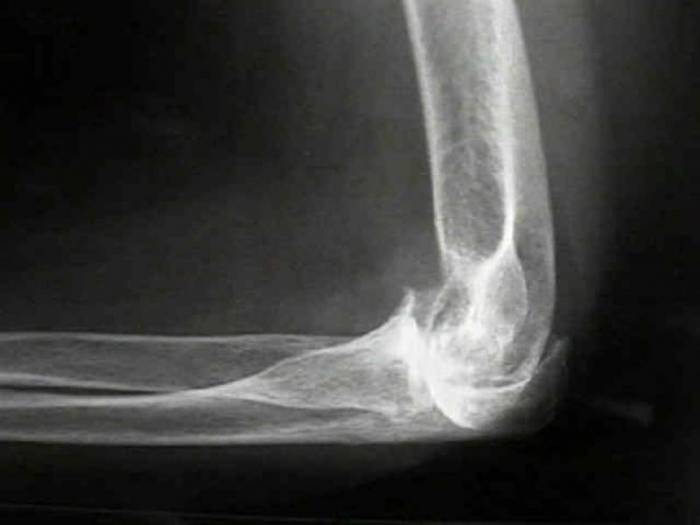

На первых этапах прогрессирования субхондрального остеосклероза суставных поверхностей костей верхних конечностей у больного во время сгибания и разгибания рук появляется хруст, не сопровождающийся болью.

Вскоре возникает ощущение наличия инородного тела, что мешает привычному движению локтевого сустава. При явном искажении сустава невозможно разогнуть руку, а попытка сделать это вызывает ощутимую боль.